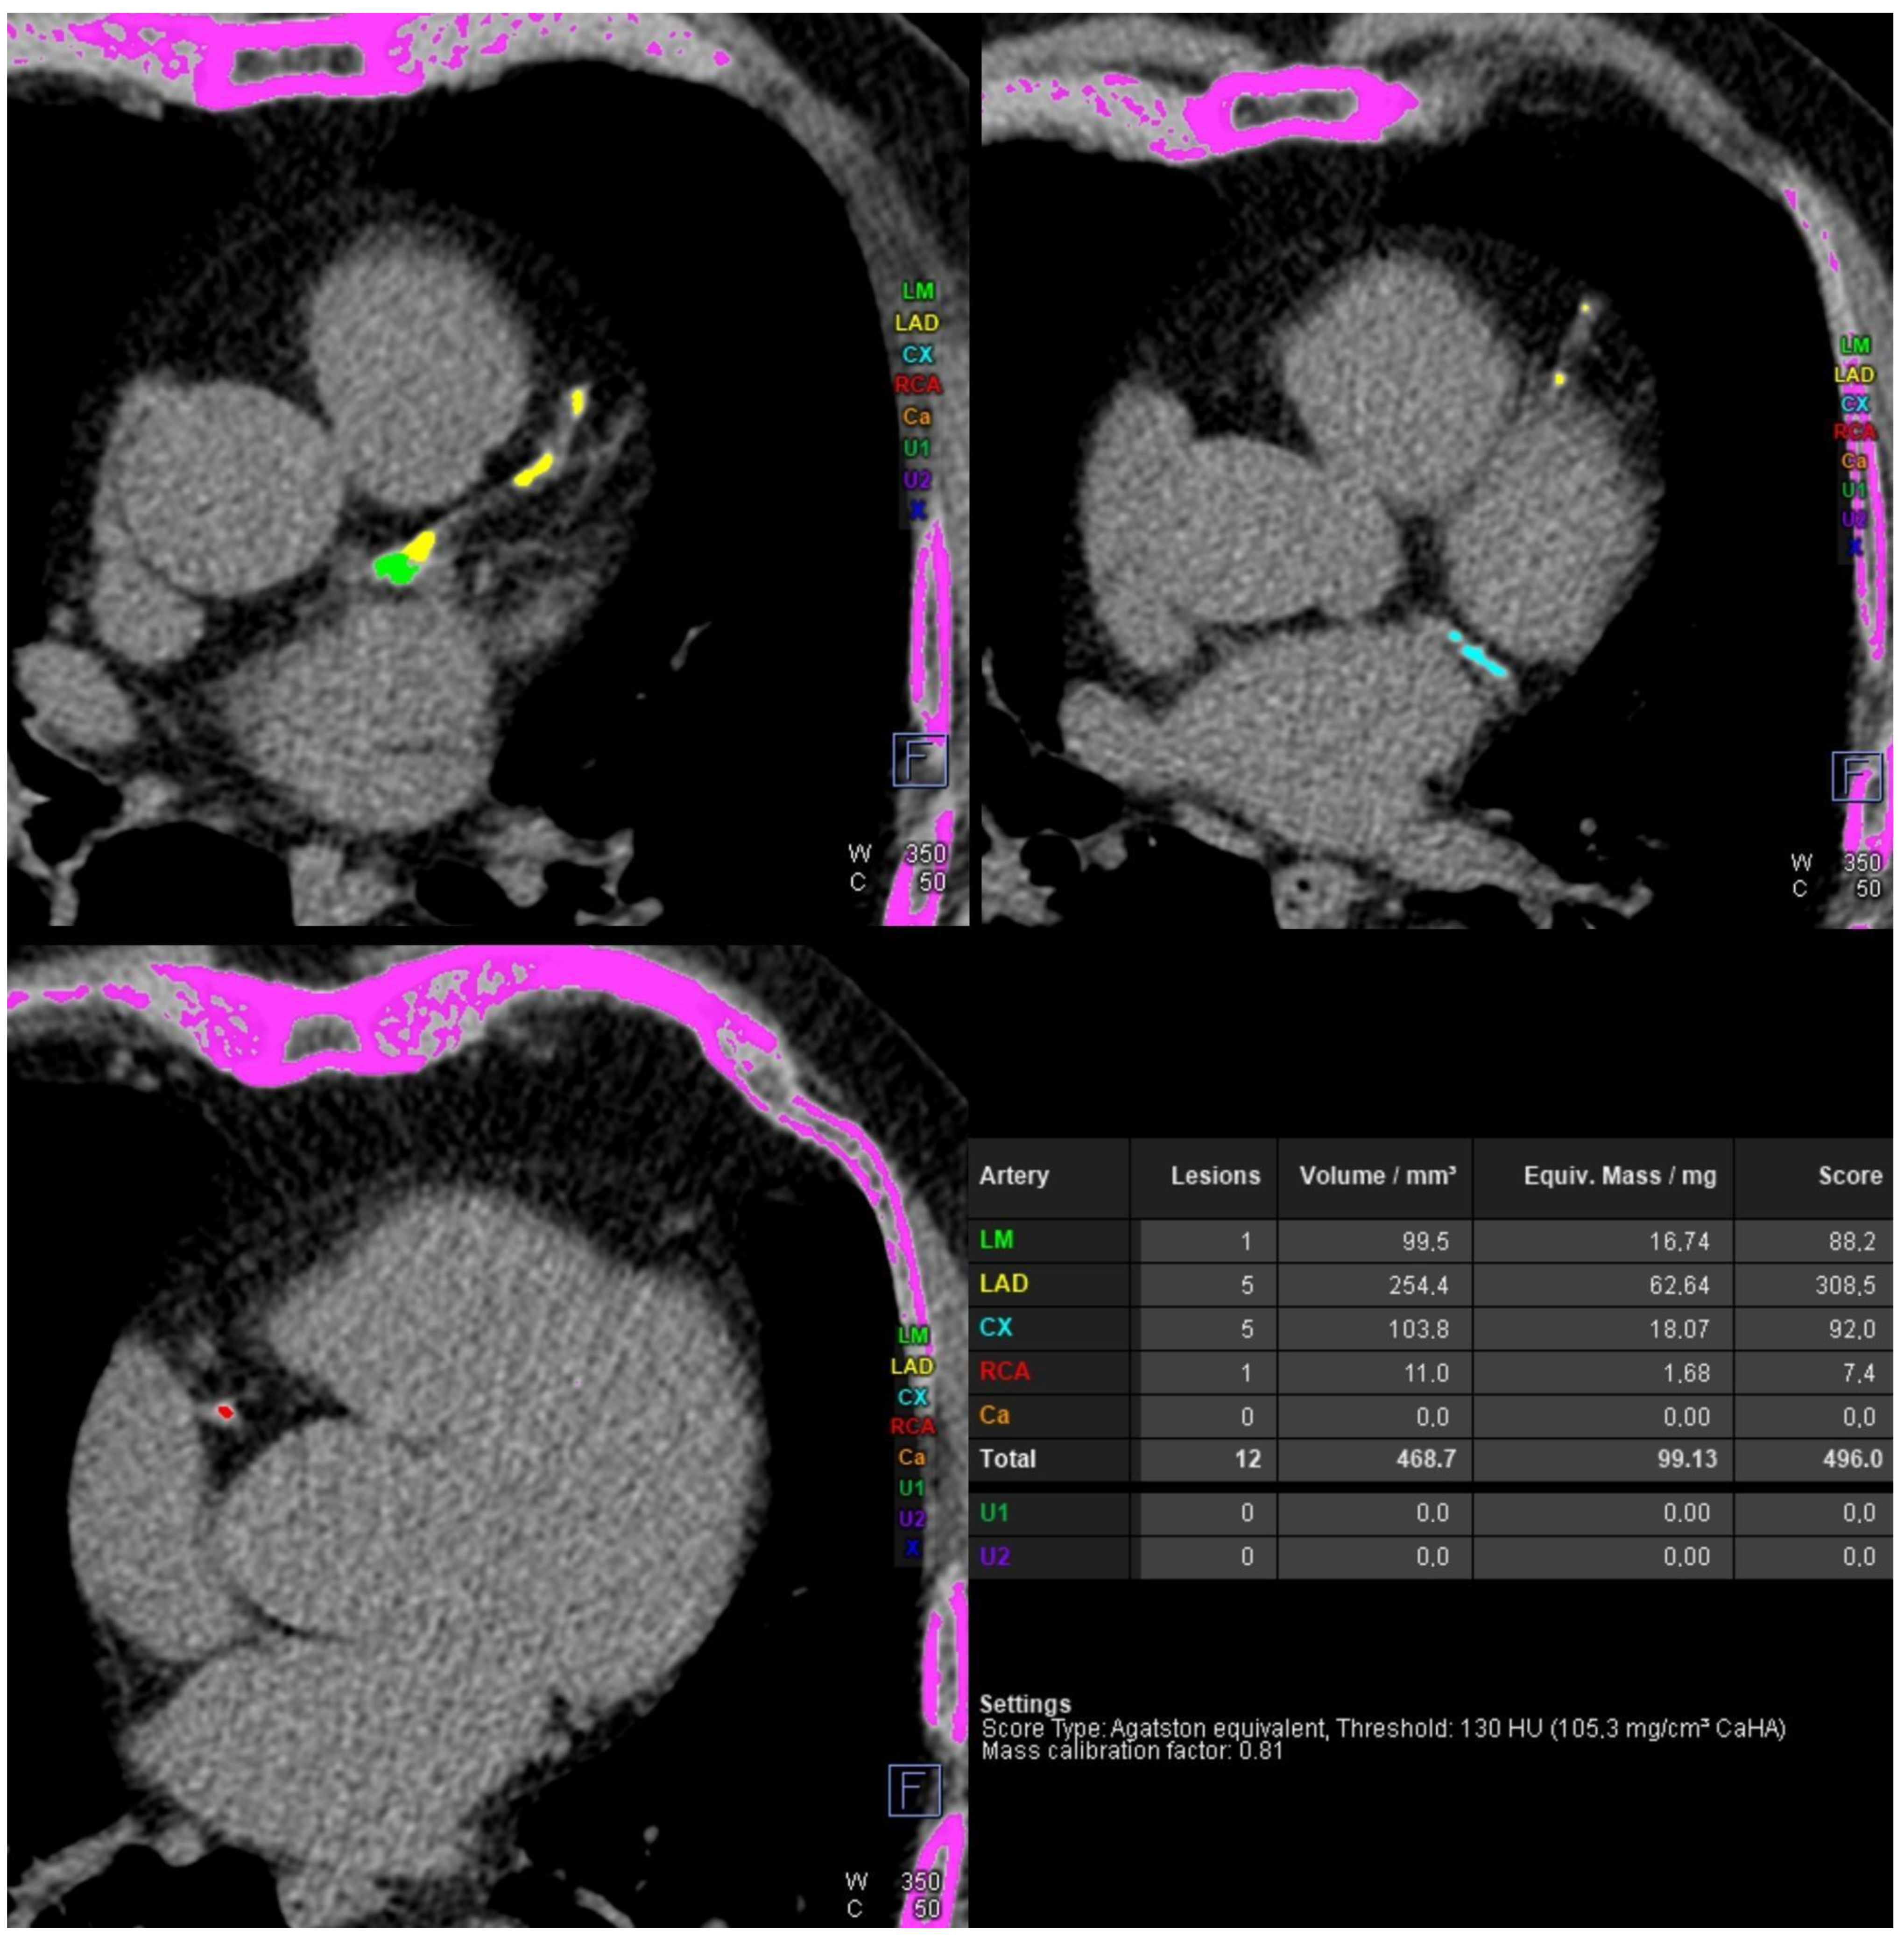

Kugel’s Artery in Coronary Computed Tomography Angiography in a Patient with Left Main Subtotal Stenosis

Gać, P.; Głuszczyk, A.; Plizga, J.; Bińczyk, W.; Dróżdż, O.; Poręba, R. Kugel’s Artery in Coronary Computed Tomography Angiography in a Patient with Left Main Subtotal Stenosis. Diagnostics 2024, 14, 2142. https://doi.org/10.3390/diagnostics14192142